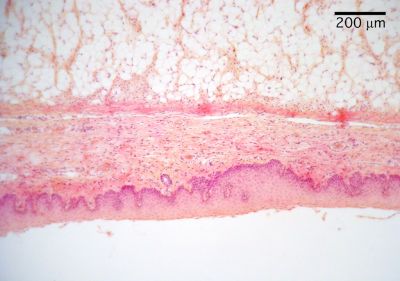

Epiglottis - histology slide

This is a histology slide of the bottom surface of the epiglottis. 100X magnification.

Histology slide courtesy of William L. Todt, Ph.D. at Concordia College, Moorhead, Minnesota.